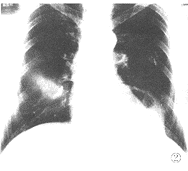

图2,3 左心尖外缘示有含气液囊腔。